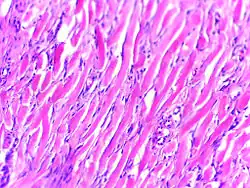

Keloid, also known as keloid disorder and keloidal scar,[1] is the formation of a type of scar which, depending on its maturity, is composed mainly of either type III (early) or type I (late) collagen. It is a result of an overgrowth of granulation tissue (collagen type III) at the site of a healed skin injury, which is then slowly replaced by collagen type I. Keloids are firm, rubbery lesions or shiny, fibrous nodules, and can vary from pink to the color of the person's skin or red to dark brown. A keloid scar is benign and not contagious, but sometimes accompanied by severe itchiness, pain,[2] and changes in texture. In severe cases, it can affect the movement of the skin. In the United States, keloid scars are seen 15 times more frequently in people of sub-Saharan African descent than in people of European descent.[3] There is a higher tendency to develop a keloid among those with a family history of keloids and people between the ages of 10 and 30 years.[4]

Pathology

Histologically, keloids are fibrotic tumors characterized by a collection of atypical fibroblasts with excessive deposition of extracellular matrix components, especially collagen, fibronectin, elastin, and proteoglycans. Generally, they contain relatively acellular centers and thick, abundant collagen bundles that form nodules in the deep dermal portion of the lesion. Keloids present a therapeutic challenge that must be addressed, as these lesions can cause significant pain, pruritus (itching), and physical disfigurement. They may not improve in appearance over time and can limit mobility if located over a joint.[16]